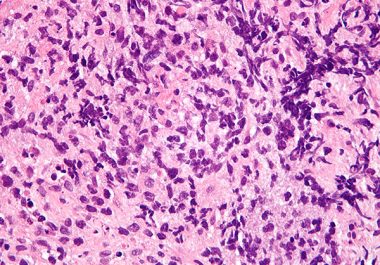

Targeting Leukemia in Older Patients

The FDA recently approved two molecularly targeted therapeutics for treating patients newly diagnosed with acute myeloid leukemia (AML) who...